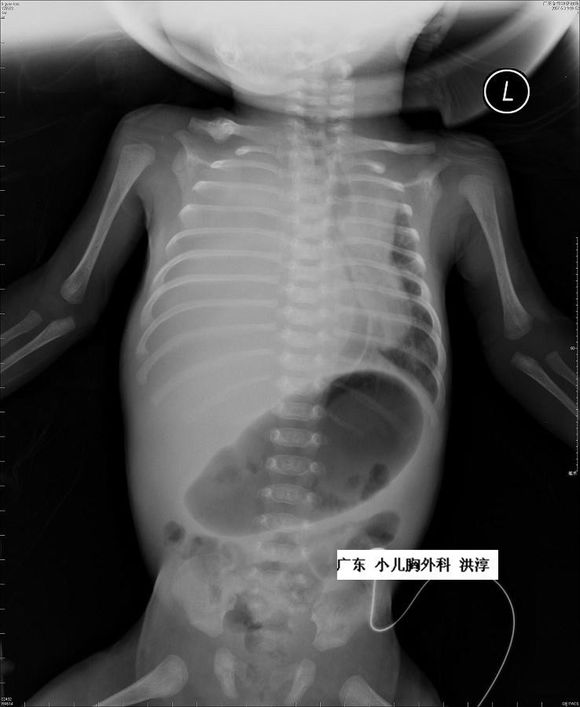

对于胎龄大于32周的胎儿胸腔积液,出生后在建立静脉通路,保证体循环血容量的情况下给予胸腔穿刺并密切观察可能是最好的选择。

对小于32周的FHT胎儿,有3种方式提供选择:胸腔穿刺术、胸腔羊膜腔分流,以及胸腔-母体皮下引流。但应该注意的是,这些操作均有可能出现感染、出血、胎膜早破、早产及损伤胎儿的风险。